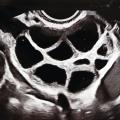

Stimulation ovarienne et ponction folliculaire

Le protocole de stimulation vise à produire une croissance multifolliculaire en limitant le risque d’hyperstimulation ovarienne. Le type de protocole et les doses de gonadotrophines ont pour but d’assurer la croissance de plusieurs ou de la totalité des follicules recrutables de la patiente (follicules antraux > 2 mm ; 5 à 20). Ce compte folliculaire antral est apprécié par échographie endo­vaginale, et les chances de réponse à la stimulation sont évaluées par des dosages de FSH en début de cycle et/ou de l’hormone antimüllérienne (AMH). Les protocoles font appel à des doses élevées de gonadotrophines de type FSH, qui favorisent le processus de recrutement et la croissance folliculaire. Le monitorage est échographique (fig. 1) et hormonal (dosage de l’estradiol [E2], le taux d’estradiol étant le reflet de la croissance folliculaire). Quand la majorité des follicules ont atteint au moins 18 mm, un déclenchement par la gonatrophine chorionique humaine (à activité LH) ou par LH est réalisé. Il induit la maturation finale des ovocytes. Les protocoles utilisent des antagonistes ou des agonistes de l’hormone de libération des gonadotrophines hypophysaires (GnRH), afin de mieux contrôler la stimulation par les gonadotrophines (type FSH) d’une même cohorte folliculaire et d’éviter le pic endogène pré-ovulatoire des gonadotrophines (LH), empêchant ainsi l’ovulation prématurée. La ponction échoguidée transvaginale des follicules est réalisée trente-quatre à trente-huit heures après le déclenchement (avec ou sans anesthésie générale). Les liquides folliculaires sont collectés dans des conditions non délétères (environnement non toxique : rinçages après désinfection locale, aiguilles de ponction, collecteurs et seringues ou tubes adaptés…) et acheminés au plus vite au laboratoire à 37 °C (fig. 2).